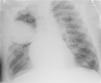

Ante sospecha de vasculitis, se inició tratamiento con 3 bolos de metilprednisolona de 500mg en días consecutivos y, posteriorment,e prednisona a 1mg/kg cada 24h. A las 72 h se produjo un cuadro de hemoptisis y anemización: se realizó radiografía de tórax y TAC torácica que mostraron hallazgos sugestivos de hemorragia alveolar bilateral y presencia de hematoma pulmonar intraparenquimatoso (figs. 1 y 2). Se inició tratamiento con bolos de 500mg/m2 de ciclofosfamida e inmunoglobulinas a 2 g/kg repartidas en 5dosis. Cinco días después apareció hemoptisis franca, anemización y gran trabajo respiratorio con traslado a UCI, donde se procedió a intubación orotraqueal y ventilación mecánica; el paciente precisó aspiración por sangrado masivo.

Las radiografías de tórax suelen ser inespecíficas: se precisa tomografía computarizada para confirmar los hallazgos. La gravedad de la situación justifica el uso del tratamiento inmunosupresor intensivo9: es habitual un tratamiento combinado con glucocorticoides y ciclofosfamida, azatioprina, metotrexato o rituximab. También se ha constatado la plasmaféresis como opción terapéutica.